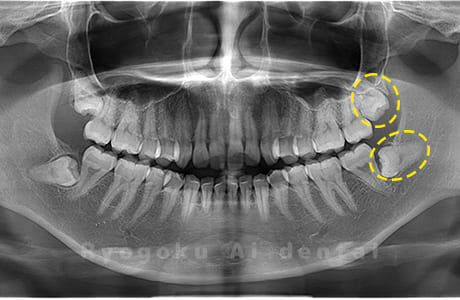

Case03

- 原因

- 上顎、下顎の親知らず

- 治療内容

- 上下4本の親知らずを抜歯したケースです。

<リスク・副作用>

手術後は痛み、腫れ、痺れなどの副作用が生じる場合があります。